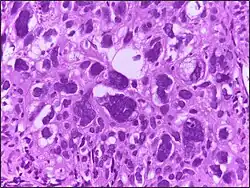

Glioblastoma | Biopsy specimen of a Glioblastoma showing extensive cell pleomorphism | Category: Histopathology of glioblastoma | glioblastoma |

![]() |